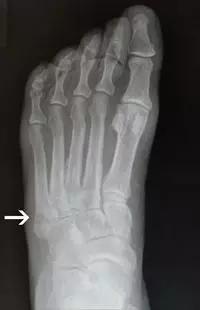

14.第五跖骨骨折

第五跖骨基底部骨折的不同类型:Stress 骨折;Jones 骨折:第五跖骨基底部以远 1 英寸内的骨折称为 Jones 骨折; Avulsion 骨折。

Jones 骨折正位片(来源:Radiopaedia)

Jones 骨折斜位片(来源:Radiopaedia)

第五跖骨骨折还有 dancer’s fracture。

dancer’s fracture 正位片(来源:footEducation)

dancer’s fracture 侧位片(来源:footEducation)